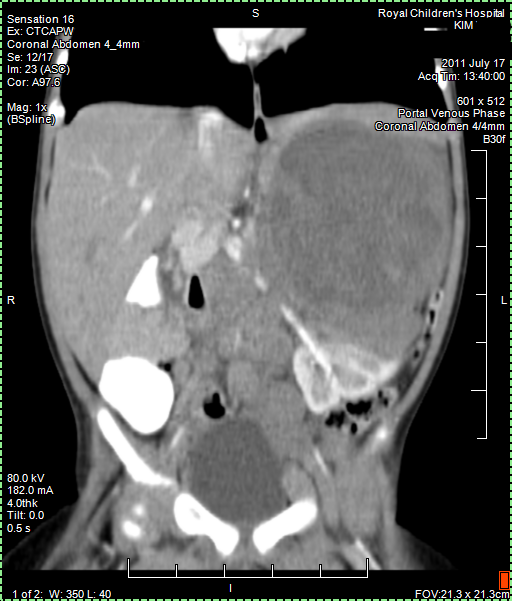

CT (CAT scan) abdomen under anaesthetic, confirms cancer. We await the Radiology Report. There is no way knowing what kind of cancer, but it is suspected maybe Neuroblastoma. We learn that there are different types of Neuroblastoma some of which are low risk and can easily be treated or removed. It is very worrying not knowing more.

Papa collected copy of CT (CAT) scan images from Radiology. Looking at them it seems that the main tumour shrank from around 11 cm to 6 cm and there is less evidence of Nodes. But we have to await Radiology Report to be sure about this positive news. Lets hope Papa is right.

Today we got the Radiology Report back of the 25 August CT (CAT) scan. Papa still has a few remaining questions about it but it confirmed that the tumour shrank as papa thought to see himself from the images. Good news!